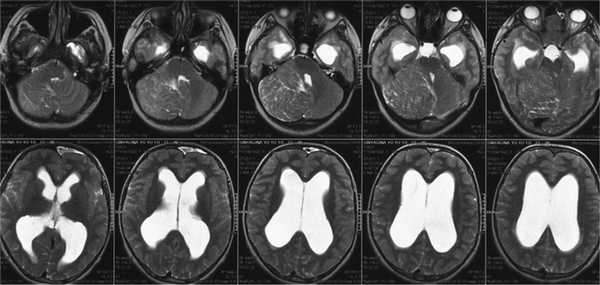

В НИИ нейрохирургии поступила больная С., 17 лет. За несколько месяцев до госпитализации стала отмечать шаткость при ходьбе, периодическую головную боль. В неврологическом статусе выявлялась окклюзионная, общемозговая, а также выраженная мозжечковая симптоматика. Из анамнеза известно, что в 2002 г. была произведена струмэктомия по поводу опухоли щитовидной железы, в связи с чем принимала L-тироксин. С 2006 г. наблюдалась по поводу макроцефалии. При проведении МРТ головного мозга выявлены объемное образование правой гемисферы мозжечка и окклюзионная гидроцефалия с признаками перивентрикулярного отека (рис. 1). По результатам КТ в сосудистом режиме сделано предположение о наличии артериовенозной мальформации правой гемисферы мозжечка (рис. 2). Для уточнения диагноза проведена церебральная ангиография, в ходе которой диагноз артериовенозной мальформации не подтвердился (рис. 3).

Рис. 1. МРТ в режиме Т2. Гиперплазия правого полушария мозжечка. Окклюзионная гидроцефалия. Рис. 2. СКТ-ангиография. Определяется расширенная окципитальная вена, которая ошибочно была принята за артериовенозную мальформацию. Рис. 3. Правосторонняя вертебральная ангиография. Боковая (а) и прямая (б) проекция. Отмечается некоторое смещение вверх и медиально от начального отрезка правой задней мозговой артерии, смещение за среднюю линию правой задней нижней мозжечковой артерии. Каудальная петля ее опущена в позвоночный канал. Широкое расположение полушарных ветвей правой верхней мозжечковой артерии.

В НИИ нейрохирургии пациентке была выполнена повторная МРТ, подтвердившая ранее выявленную патологию (рис. 4).

![]()

Рис. 4. На МРТ головного мозга в режиме Т2 в аксиальной проекции — «пестрый» рисунок правого полушария мозжечка с увеличением его размеров. IV желудочек смещен влево, сужен. III и боковые желудочки расширены.

При ретроспективном анализе снимков, выполненных в 2006 г. по поводу макроцефалии, в правой гемисфере мозжечка установлено объемное образование небольшого размера, практически не отличающееся от вещества мозжечка (рис. 5).

Рис. 5. МРТ головного мозга в аксиальной проекции, режим Т2 (2006 г.).

Таким образом, можно было сделать вывод, что значительное увеличение ганглиоцитомы произошло в пубертатный период. По поводу клинических и рентгенологических признаков окклюзионной гидроцефалии с перивентрикулярным отеком больной произведено вентрикулоперитонеальное шунтирование. После разрешения гидроцефалии у пациентки сохранялось опущение миндаликов мозжечка в большое затылочное отверстие (рис. 6, 7), в связи с чем была выполнена декомпрессия краниовертебрального перехода и биопсия образования мозжечка (рис. 8).